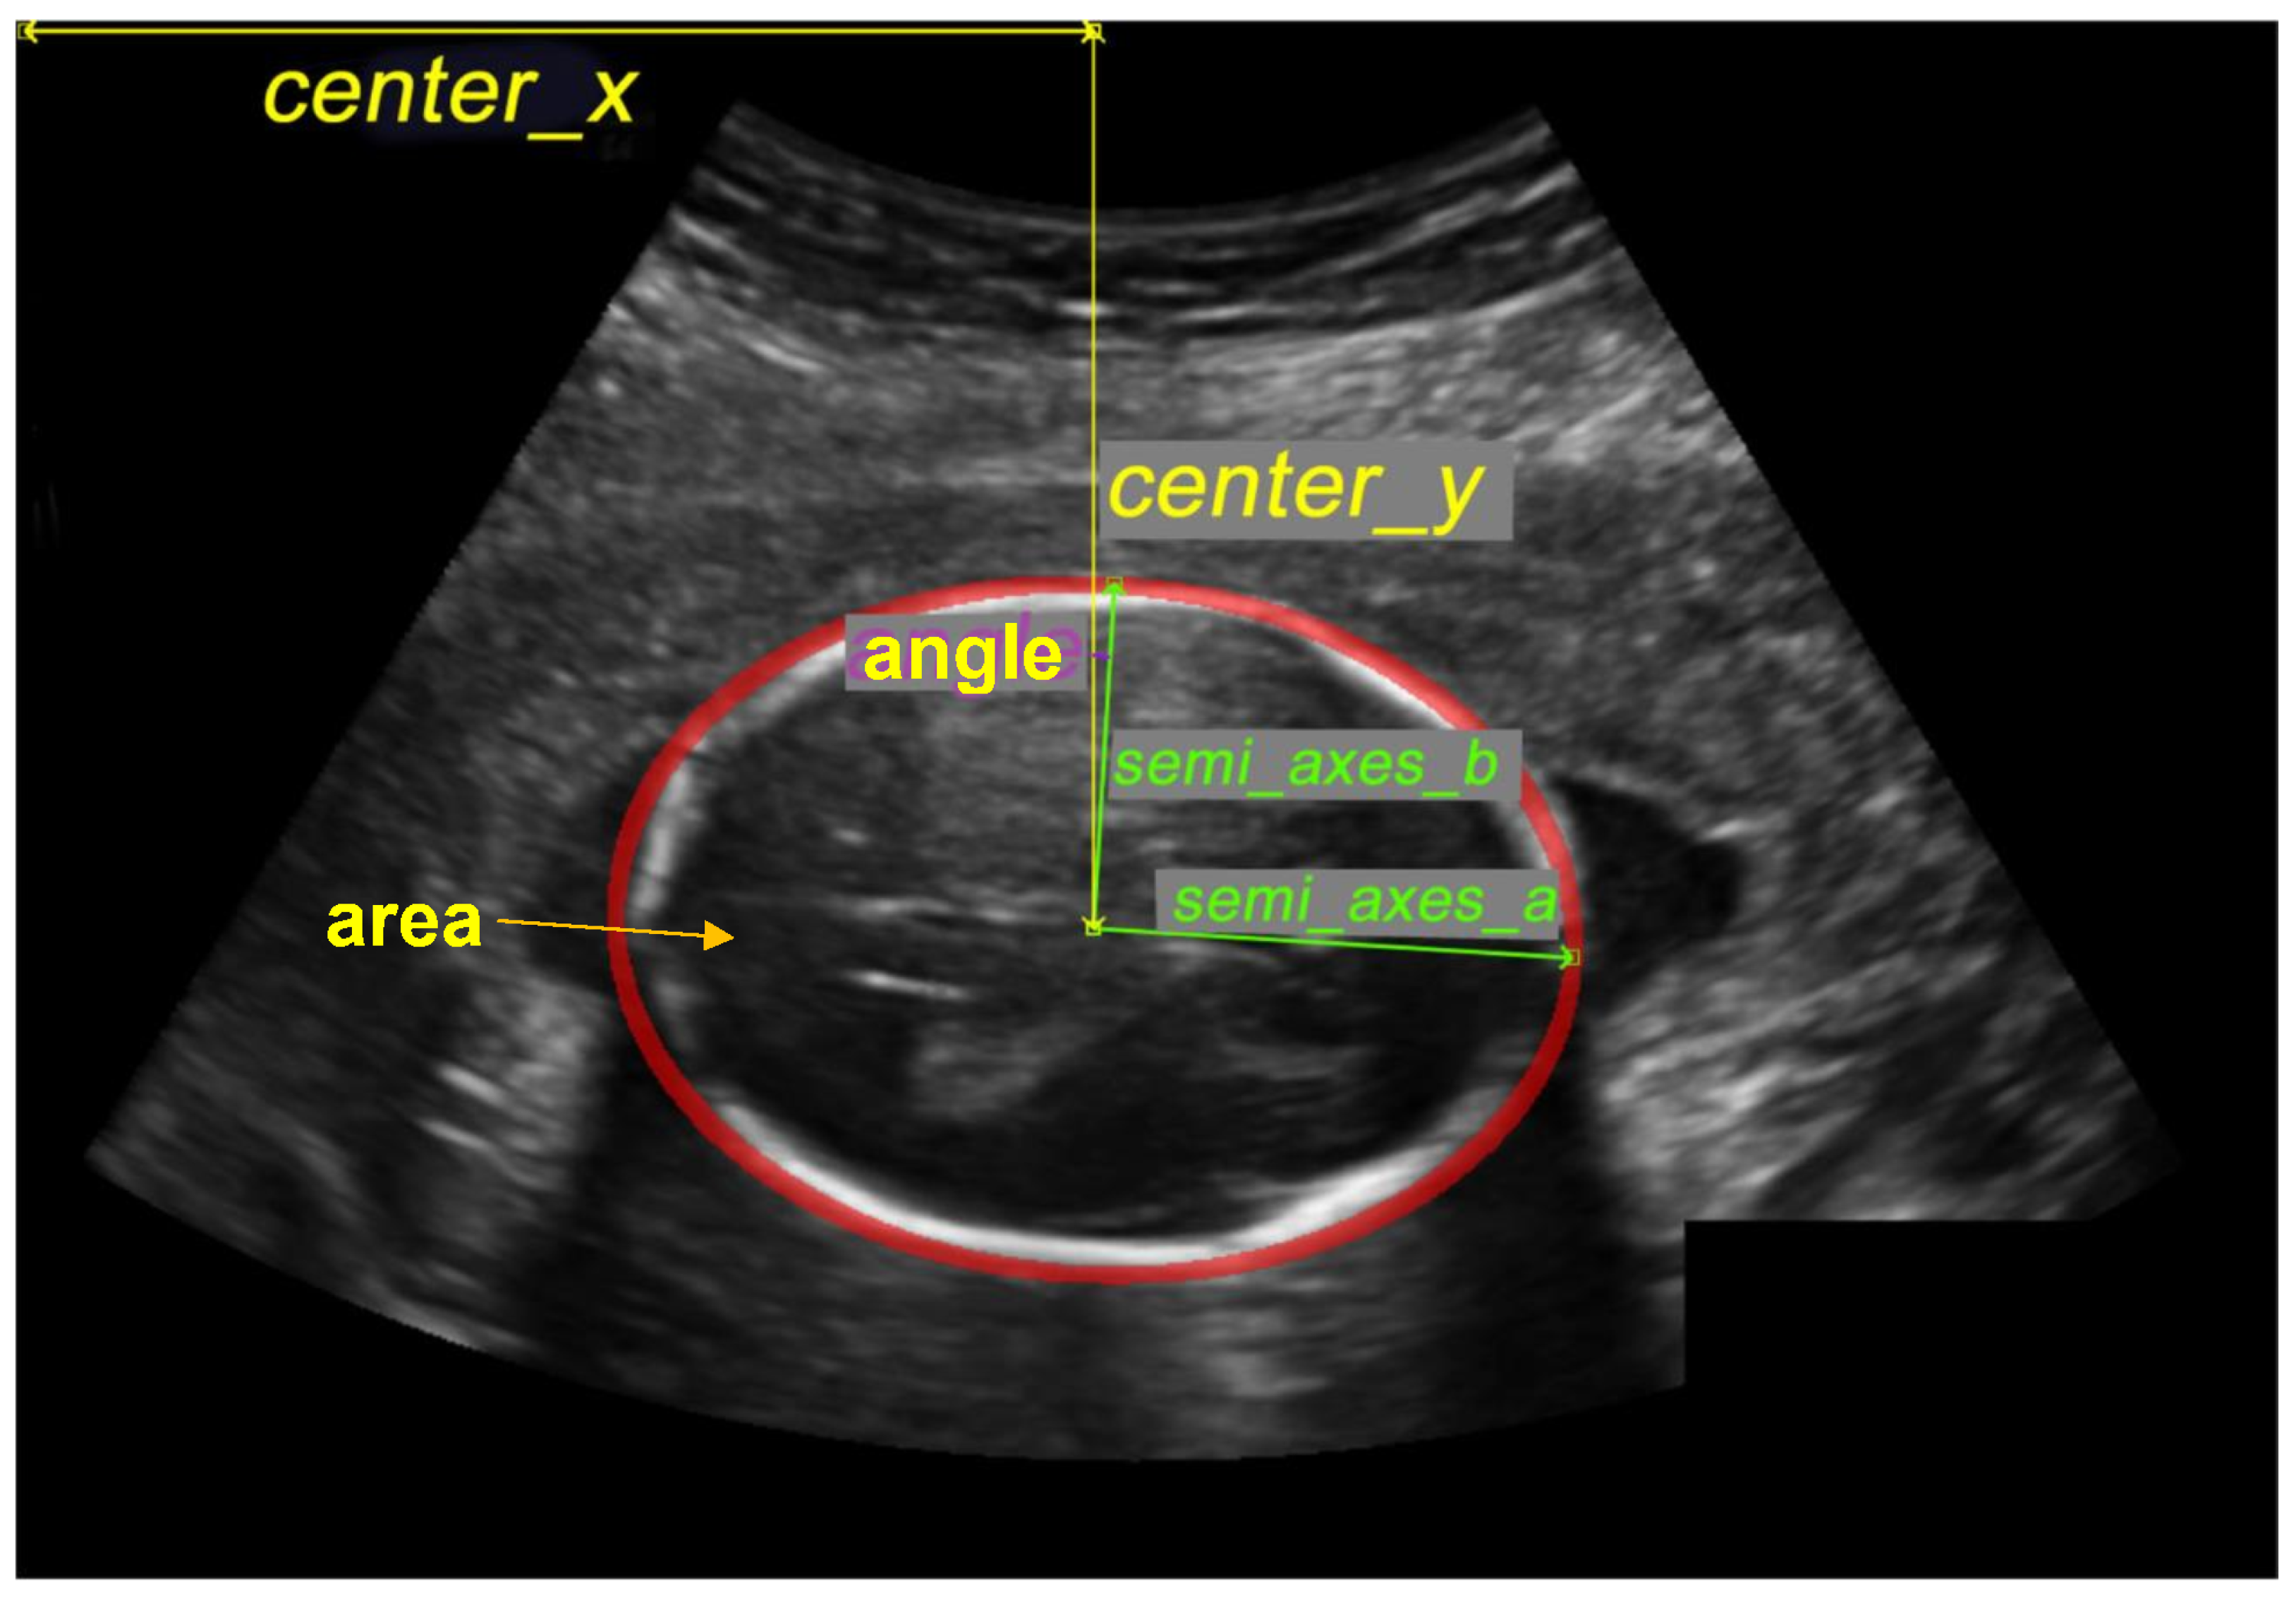

- center x: represents the length in millimeters between the image’s beginning pixel on the x-axis and the ellipse’s middle pixel.

- center y: represents the length, in millimeters, between the image’s beginning pixel on the y-axis and the ellipse’s middle pixel.

- semi-axes a: Once the ellipse’s center is determined, the semi-axes determine the radius’s maximum value based on the distance between the ellipse’s middle and its farthest point.

- semi-axes b: Once the ellipse’s center is determined, the semi-axes determine the radius’s minimum value based on the distance between the ellipse’s middle and its nearest point.

- angle: contains the radian value of the angle formed by the center y and the semi-axis b.

- area: is the size of the area in millimeters that represent the fetal head.